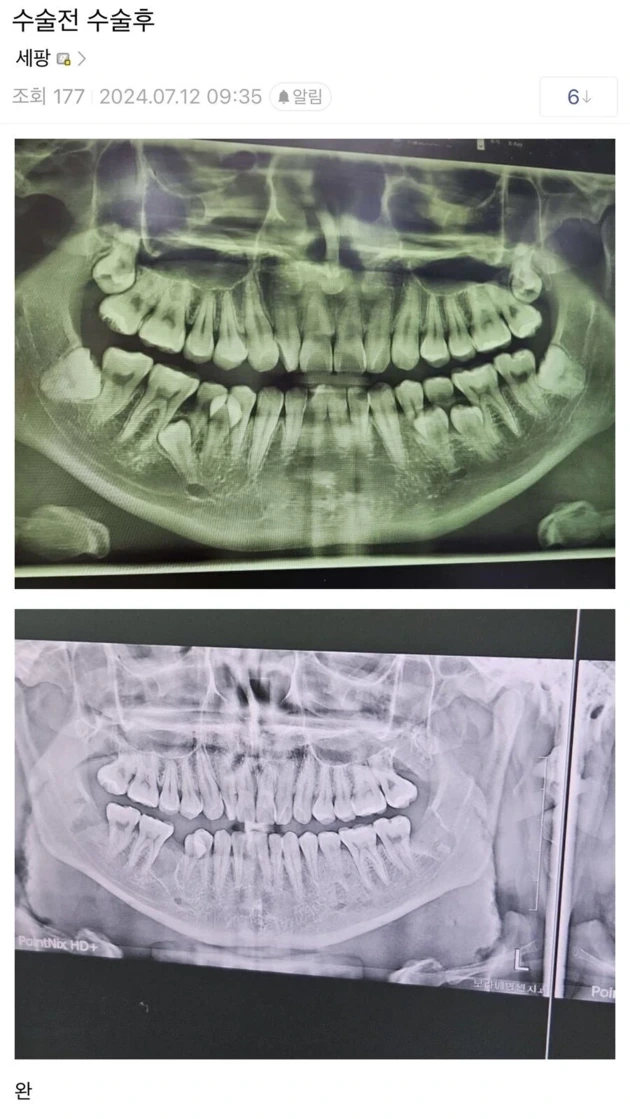

레전드였던 사랑니 수술 전후 비교

닉네임리플리등록 날짜&시간2025.03.06

환자도 울고 의사도 울고

게시글 이미지 개수2